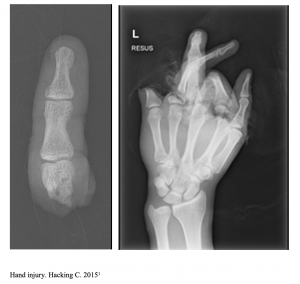

A 28-year-old male presents as a transfer from an urgent care with report of left-hand injury. He is a construction worker and was using a table saw when he injured his left hand. The amputated part is wrapped in a plastic bag. He is right-handed.

Imaging from outside hospital are below:

What is the patient’s diagnosis? What’s the next step in your evaluation and treatment?

Answer: Finger Amputation

- Hand and finger x-rays, including amputated part